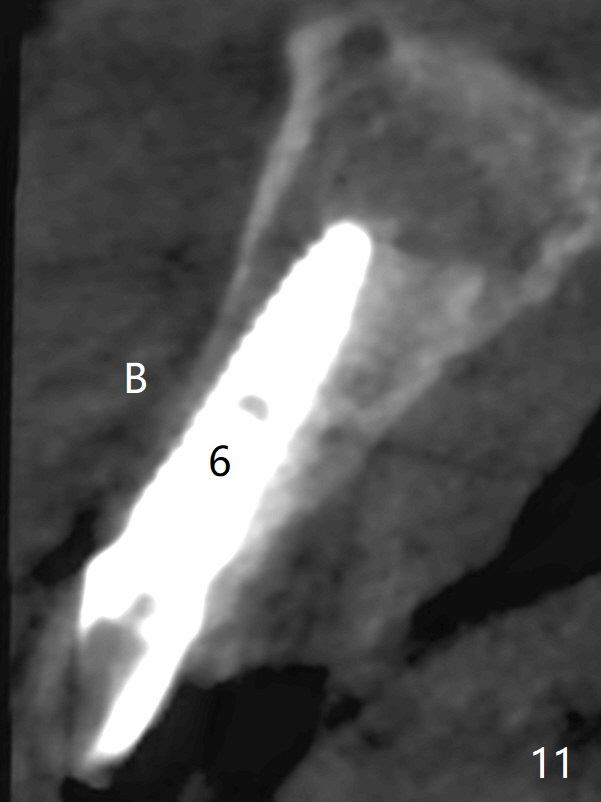

To have enough clearance for the splinted provisional at #6-12 (Fig.1 *), composite has been placed in the posterior teeth (bilateral, *, Fig.2). When the composite is removed, there is no clearance between the implants/abutments of #7 or 10 (Fig.3). Incision is made with removal of the 1-piece implant at #7; there is enough bone to move the osteotomy buccal (Fig.4 arrowhead). When the same implant is placed buccal (Fig.5), there is sufficient clearance for restoration (Fig.6 *), while there is still enough buccal bone left (Fig.7). When the patient returns 5.5 (for #7 and 10)/6.5 (#6,11,12) months postop, his chief complaint is tenderness lingual to #11. In fact, the abutment screw is loose at #11, while the implant at #10 has mobility (Fig.8), which is related to loss of the posterior stops (*) due to wear. There is slight bone loss mesial to #10 implant 5.5 months postop (Fig.10, as compared Fig.9). CBCT taken 5.5/6.5 months postop shows no bone loss (Fig.11-15). The 3x14 mm 1-piece implant at #10 is mobile 9 months postop and is removed and replaced by a 3.5x13 mm 2-piece one with slightly buccal osteotomy (Fig.16). PAs are taken prior to impression (Fig.17,18). The abutment at #12 is loose (<). More composite needs to be added to the occlusal surface of the upper posterior teeth. Finally the patient agrees to have crowns for the upper posterior teeth.